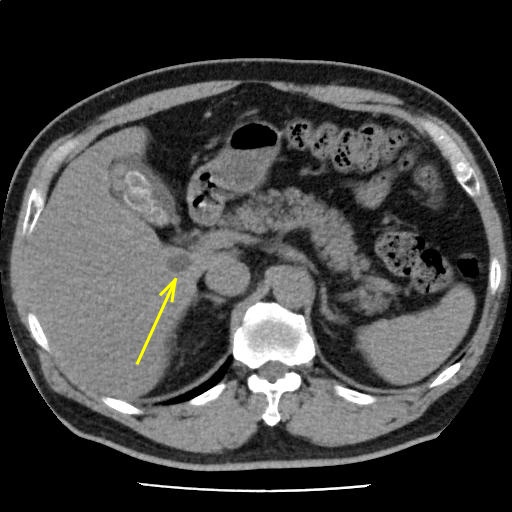

脂肪肝を認め、肝嚢胞を伴う。

胆石を認める。